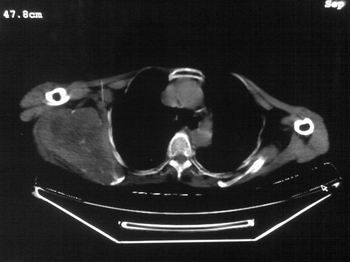

以下是引用zhangxu5888在2007-9-11 16:25:00的发言:[br]有侧肩胛骨溶骨性破坏且见软组织成分,增强软组织强化明显,中央见低密度坏死区!根据病史10年,考虑良性肿瘤恶性变!性质待定!

以下是引用老爱克斯新网客在2007-9-11 18:22:00的发言:[br]应该是良性肿瘤恶变,但因晚期破坏严重不能见到原来肿瘤征象无法判断,